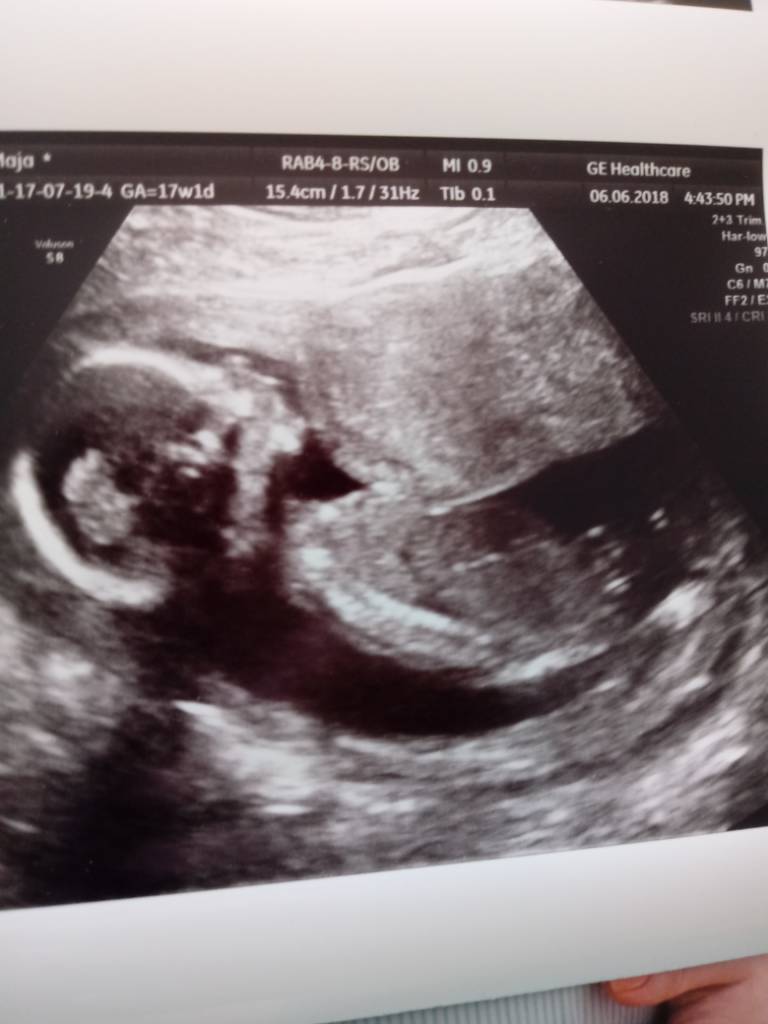

U mnie też wszystko ok. Lekarz młodego zmierzył 13cm. Wielkość z obwodu brzuszka, głowy i długości kości udowej na 17+1 czyli idealnie

Pyta mnie czy mówił mi płeć ostatnio. Ja mówię że tak, a on to niech mi Pani nie mówi. Zobaczymy.

Młody się wiercił i rozciągał a doktor mówi: chłopaczek. Tak mówiłem ostatnio?

Ja mówię że tak